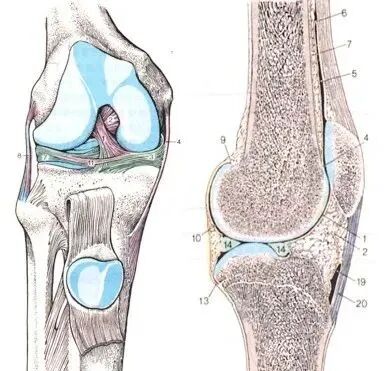

膝关节

股骨远端、胫骨近端、髌骨,是构成膝关节主要的骨组织。其中,股骨和胫骨构成一个关节面,而股骨和髌骨构成一个关节面(髌股关节)。正常情况下,膝关节在弯曲运动时,髌骨是在股骨的凹槽(股骨滑车)里上下移动。

髌 骨

1.髌骨的解剖

• 全身*的籽骨

• 上*与股四头肌相连

• 下*由髌韧带固定于胫骨结节

• 7个关节面

• 仅下1/4为非关节面部分

• 伸膝装置的支点

处于皮下,只有皮肤、很薄的皮下组织和髌前滑囊覆盖,易受直接暴力撞击。

髌骨的关节面与股骨的内外髁相互形成关节,膝关节屈伸时,髌骨在股骨内外髁之间滑动。髌骨不*助于保护膝关节,还通过减少移动膝盖所需的力量,帮助四头肌更有效地工作。